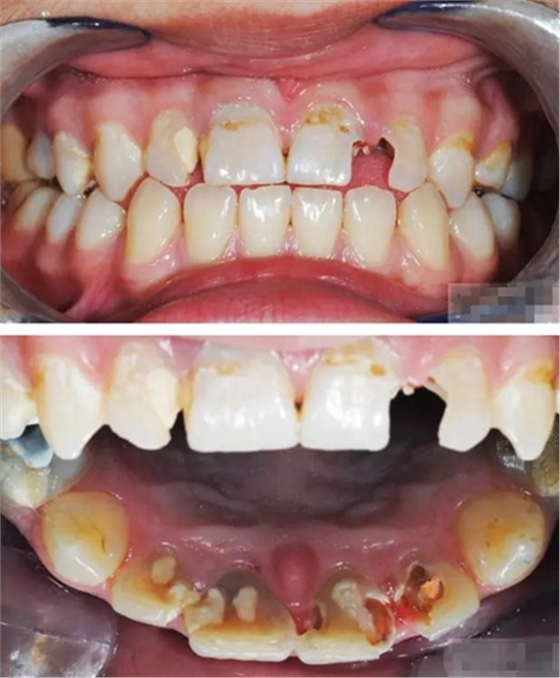

【主訴】上前牙充填物脫落兩個(gè)月

【病史】上前牙一年前行根管治療,充填物部分脫落,自覺影響美觀,從不敢笑,要求先行樹脂修復(fù)。(年齡:14歲)

【檢查】12,11,21,22,均行玻璃離子充填,各牙不同程度部分充填物脫落,探(—),叩(—),冷刺激無反應(yīng),無松動(dòng),牙齦顏色粉紅,質(zhì)地堅(jiān)實(shí)而有彈性,點(diǎn)彩正常,牙結(jié)石(—);牙髓活力測試無反應(yīng)。

【診斷】12,11,21,22牙體缺損